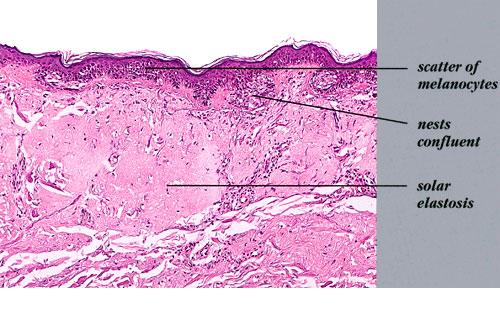

melanoma-in-situ-on-sun-damaged-skin-of-a face